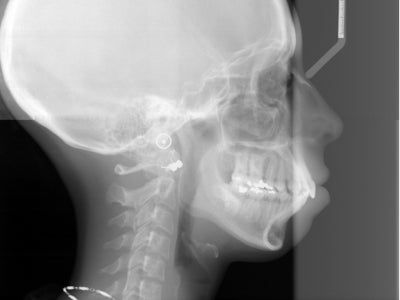

Nên phẫu thuật hàm hay niềng răng cho trường hợp hô vẩu, cười hở lợi

Tôi chuẩn bị niềng răng, dự tính hàm trên niềng răng mặt trong còn hàm dưới niềng răng mắc cài truyền thống. Một vài bác sĩ khuyên tôi nên phẫu thuật hàm nhưng cũng có 1 vài bác sĩ nói tôi chỉ cần nhổ 4 răng và cắm minivis là đủ để chữa hô vẩu, đồng thời giảm mức độ cười hở lợi. Dưới đây là hình ảnh phim X-quang của tôi. Tôi muốn hỏi thêm là nếu tôi nhổ 4 răng thì sau bao lâu đóng khoảng trống lại được vì tôi là diễn viên nên rất quan tâm điều này? Cảm ơn bác sĩ.